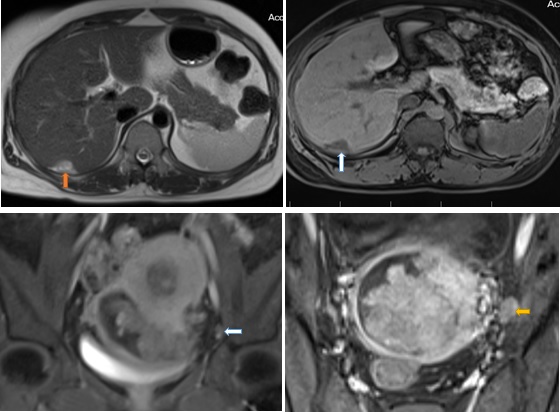

Kết quả MRI: Từ buồng nội mạc lan tới âm đạo có khối choán chỗ kích thước # 68 x 86 x 72 mm (trước sau- cao -ngang), tín hiệu trung gian trên T2W, thấp trên T1W, hạn chế khuếch tán, bờ ngoài u không đều, đa thuỳ, u xâm lấn không thấy cổ tử cung. U có cuống xuất phát từ vùng đáy tử cung. Sau tiêm Gd, u bắt thuốc tương phản mạnh không đồng nhất. Dọc vách chậu hai bên có vài hạch hình tròn kích thước # 9 x 15 mm, bờ ngoài không đều, bắt thuốc tương phản kém. Rải rác phúc mạc vùng chậu có vài nốt bất thường tín hiệu kích thước </= 17 x 22 x 15 mm, bờ đa cung, hạn chế khuếch tán, bắt thuốc tương phản không đồng nhất.Vùng phía sau gan ngay hạ phân thuỳ VIII có nốt bất thường tín hiệu kích thước # 27 x 20 mm, tín hiệu trung gian trên T2, thấp trên T1, bắt thuốc tương phản kém sau tiêm, khối này ấn lãm bờ gan

Kết luận: Hình ảnh gợi ý sarcoma cơ tử cung xâm lấn cổ tử cung. Chẩn đoán phân biệt: Ung thư nội mạc tử cung giai đoạn IVB (FIGO), hạch vách chậu hai bên dạng hạch di căn, nốt phúc mạc vùng chậu nốt ở sau gan phải ấn lõm bờ gan nghĩ mô u reo rắc

Hình 5: Hình trên trái: nốt reo rắc phúc mạc bờ gan hạ phân thùy VII, tín hiệu cao nhẹ trên T2 ( mũi tên cam); hình trên phải: sau tiêm Gd trên xung T1 vibe FS tổn thương bắt thuốc tương phản kém ( mũi tên trắng) ; Hình dưới trái: Nốt bắt thuốc phúc mạc vùng chậu trên hình T1 vibe FS sau tiêm Gd ( mũi tên trắng); Hình dưới phải: T1 FS Sau tiêm Gd hạch bắt thuốc tương phản không đồng nhất (mũi tên vàng)